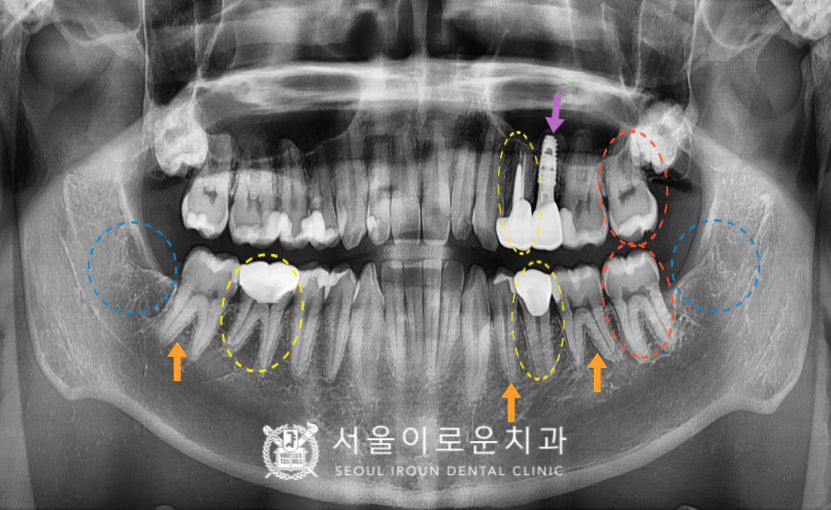

오늘 소개해드릴 분은 30대 남성분으로,

왼쪽 위아래 어금니와

오른쪽 아래 어금니가

아파서 치료를 원하시며

아래 사랑니도 빼고 싶다며

본.원을 찾아주셨는데요.

구강 내 상황을 체크해 보니

치아와 치아 사이에

충치가 있는 부위를

다수 관찰 할 수 있었으며,

기존 크라운 보철물과

아말감 수복물 하방으로

2차 우식이 관찰되는 부위도

확인할 수 있었습니다.

오른쪽 위 치아를 제외하고는

다수의 치아의 치료가 필요하였답니다..!

하나하나 살펴보도록 하겠습니다!

✔ 왼쪽 위 두 번째 작은 어금니(#25) – 보라색 화살표

: 발치 후 즉시 임플란트

✔ 왼쪽 위 첫 번째 작은 어금니(#24),

왼쪽 아래 두 번째 작은 어금니(#35),

오른쪽 아래 첫 번째 큰 어금니(#46) – 노란색 동그라미

: 크라운 (필요시, 신경치료)

✔ 왼쪽 위아래 두 번째 큰 어금니(#27,37) – 빨간색 동그라미

: 기존 아말감 제거 후 인레이

✔ 왼쪽 아래 첫 번째 작은 어금니(#34), 큰 어금니(#36),

오른쪽 아래 두 번째 큰 어금니(#47)- 주황색 화살표

: 충치 제거 후 인레이

✔ 왼쪽, 오른쪽 아래 사랑니 (#38,48) – 파란색 동그라미

:발치